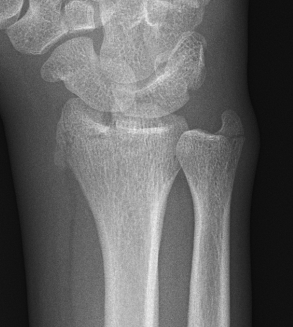

![]() |